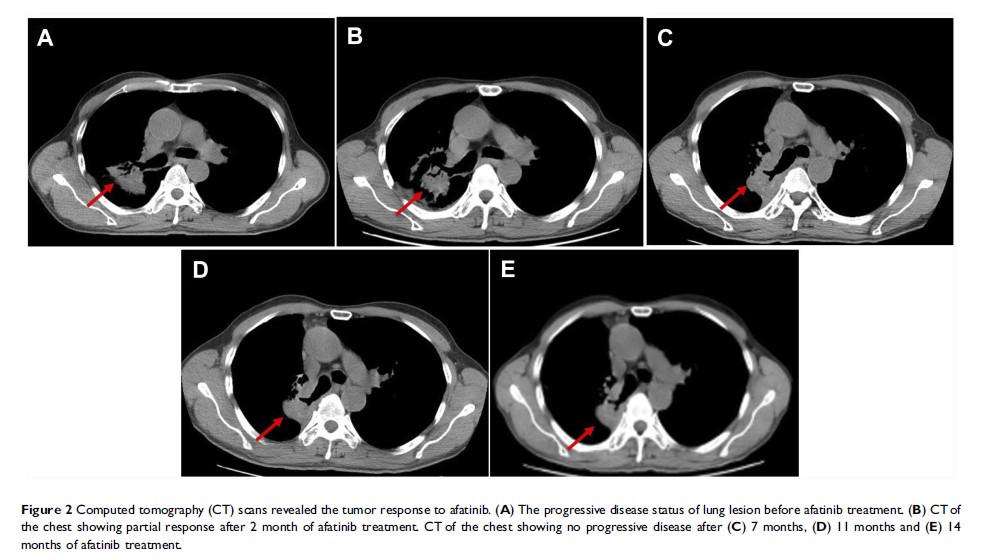

Case Report

携带 HER2 R896G 突变的非小细胞肺癌患者对阿法替尼的反应:一份病例报告